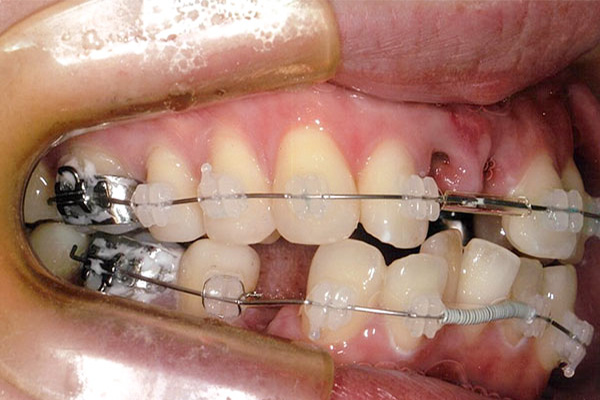

1年6ヶ月後